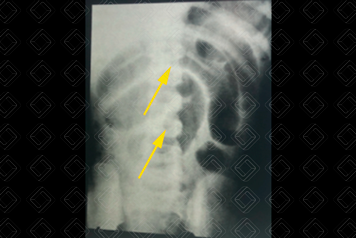

Texto alternativo para a imagem Figura 2. Créditos: Dra. Elazir Mota - Rio de Janeiro/RJ

Descrição das figuras 1 e 2: Radiografia de abdome em decúbito e ortostase. Há sinais sugestivos de um quadro obstrutivo, como ausência de gás no reto (asterisco), níveis hidroaéreos em alturas diferentes (setas vermelhas) e o padrão chamado de alça em “U” invertido (setas amarelas). Nesse, caso trata-se de uma provável obstrução de alças de delgado (as alças estão dispostas mais centralmente na radiografia e isso sugere acometimento mais alto, ou seja, de intestino delgado).